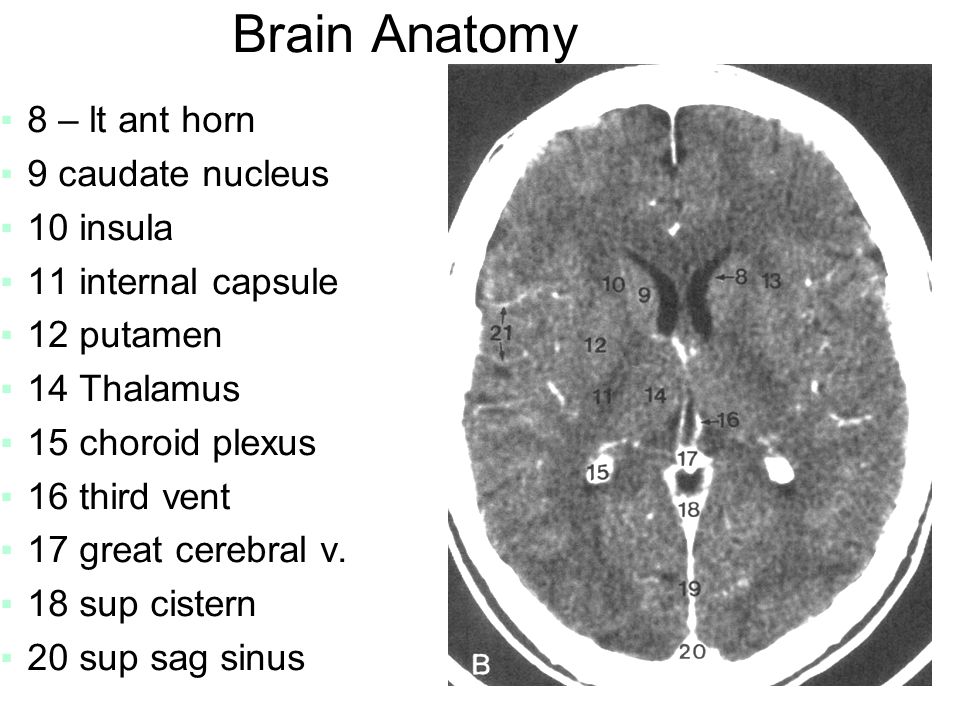

Sectional anatomy of the structures of the brain as viewed with ct mri and pet fusion imaging. It is superior to the upper pole of the right kidney whereas the left adrenal gland is anteromedial to the upper pole of the left kidney.

These labeling exercises are to aid the viewer in learning the sectional anatomy of the brain.

The cross sectional anatomy of the normal adrenal gland is identical on ct and mri. This mri brain cross sectional anatomy tool is absolutely free to use. Choose from 500 different sets of cross sectional anatomy brain flashcards on quizlet.

Mri of the brain. Anatomy of the encephalon mri in axial slices we created a brain atlas that is an interactive tool for studying the conventional anatomy of the normal brain based on a magnetic resonance imaging exam of the axial brain. Use the mouse scroll wheel to move the images up and down alternatively use the tiny arrows on both side of the image to move the images on both side of the image to move the images.